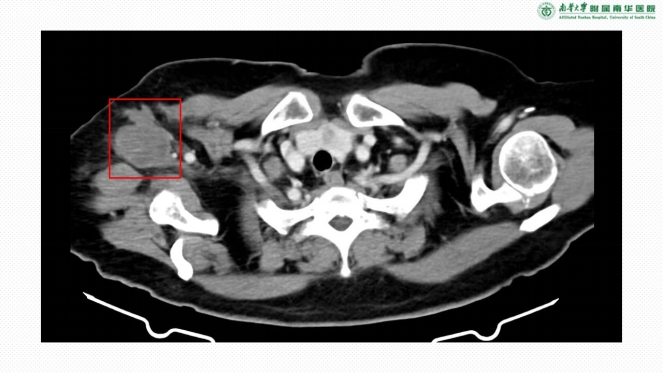

△右侧腋窝滑膜肉瘤